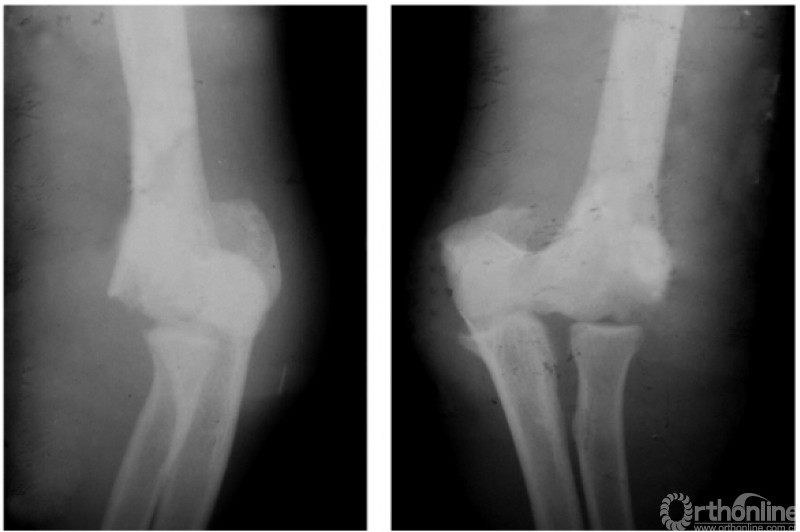

二、陈旧性肱骨髁上骨折

例1:陈旧性伸展型肱骨髁上骨折,致肘内翻畸形及前倾角消失(图7)。

图7

例2:伸展型肱骨髁上陈旧折,完全向后上移位的骨折远端,在被掀起的骨膜下成骨,已为肱骨下段重建了新的关系;而向前下移位的近折端已与尺骨近端形成骨性连接。致患肘被固定在肘曲40°位置上(图8)。

图8